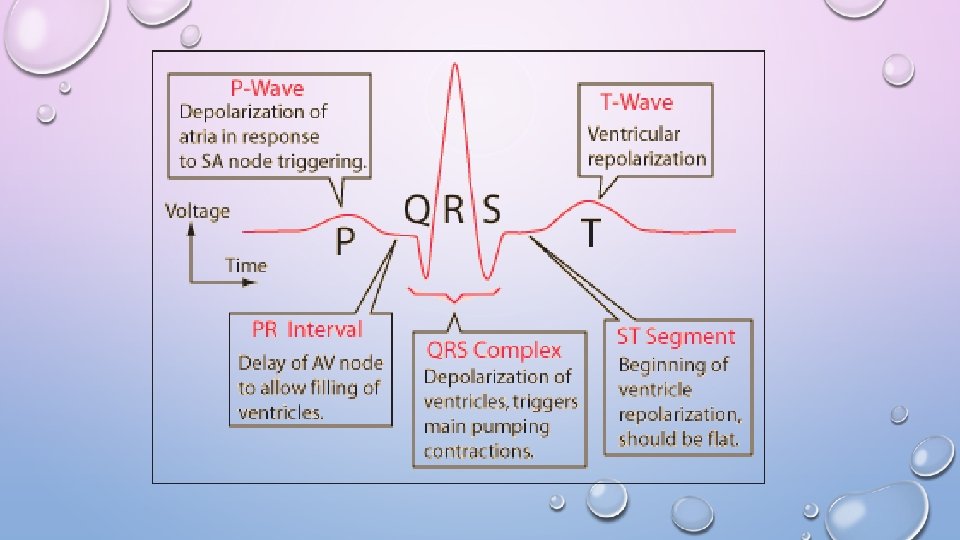

EKG/ECG • CHECK ELECTRICAL ACTIVITY OF HEART • HELP DIAGNOSING: UNEXPLAINED CHEST PAIN, HEART DISEASE, CHECK MEDICATIONS, PACEMAKERS, HIGH BLOOD PRESSURE • LAY DOWN, ELECTRODES ATTACH TO YOU, TAKES ABOUT 5 -10 MINUTES • NORMAL HEART BEAT = 60 -100 BEATS PER MINUTE • ABNORMAL = LOWER THAN 60 OR HIGHER THAN 100